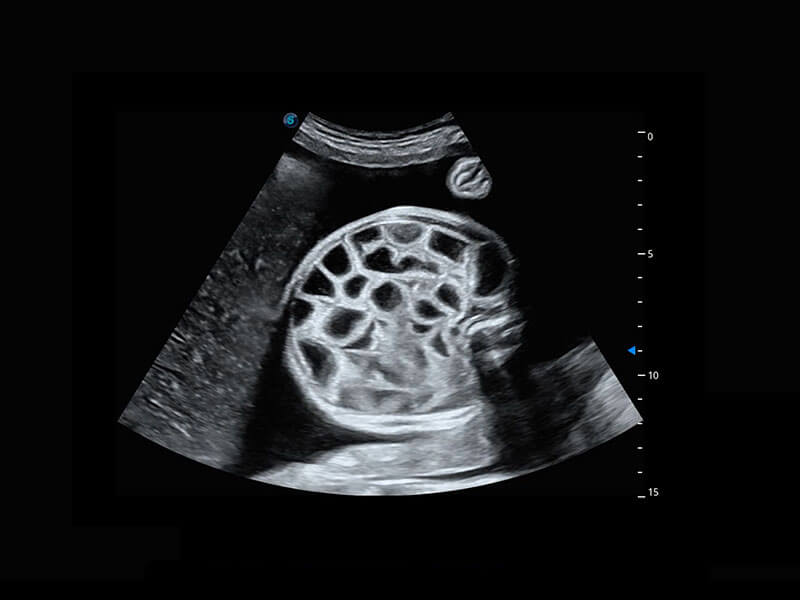

P60搭载宽频带线阵探头、宽景成像、弹性成像技术,为您提供乳腺应用方案。P60支持高频相控阵探头、线阵探头、腹部高频探头、腹部微凸探头等,丰富的探头群搭载敏感的彩色血流成像,适用于新生儿多种脏器检测要求,满足新生儿筛查需求。

新生儿肝血管癌